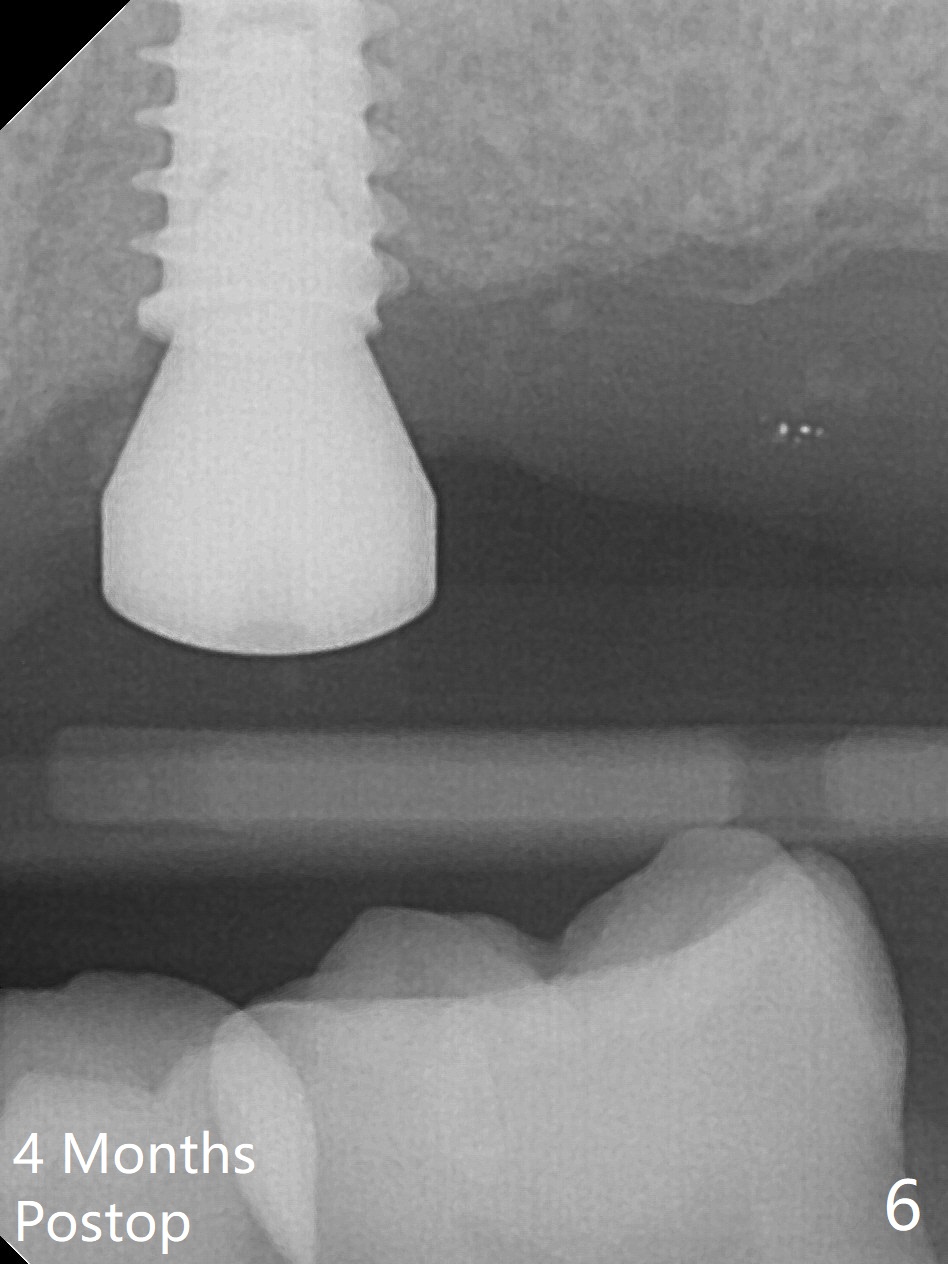

After extraction of the tooth #14 (Fig.1) and removal of granulation tissue associated with a distal fistula, a 1.6 mm drill is used to initiate osteotomy in the septum for 9 mm, followed by insertion of a 7 mm long parallel pin (Fig.2).  The length of the subsequential osteotomy is 11 mm until 4.8 mm in diameter (overprep as will be shown below).  The bone is hard so that sinus lift fails with 4.8 mm Magic Expander.  Since a 5x9 mm dummy implant is placed with stability, a definitive implant with the same dimension is chosen with >50 Ncm (Fig.3,4).  Prior to and after abutment placement, Vera graft is placed (*).  The provisional perforates with loose abutment 3.5 months postop.  A 6x4 mm healing abutment is placed.  Osteointegration occurs 4 months postop (Fig.5,6).